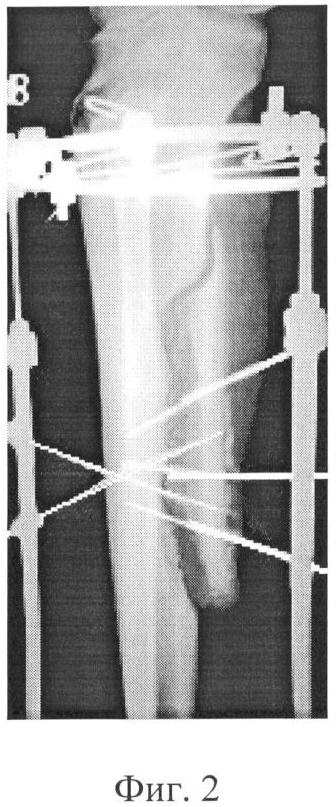

Фиг.2 – рентгенограмма голени больного на этапе стабильной фиксации;

В послеоперационном периоде, начиная с 5-го дня, осуществляли дозированную тракцию сформированного продольного отщепа большеберцовой кости в направлении, перпендикулярном ее продольной оси. Темп тракции составлял 0,5 мм в сутки, а ее продолжительность – 28 дней. После окончания перемещения отщепа тракционные спицы удалили, аппарат демонтировали. В дальнейшем до оссификации участка сформированного костного регенерата, стабильное положение отщепа поддерживали за счет дополнительных перекрестно введенных спиц. В течение всего срока лечения осложнений со стороны покровных тканей и нарушений течения остеогенеза не отмечено.